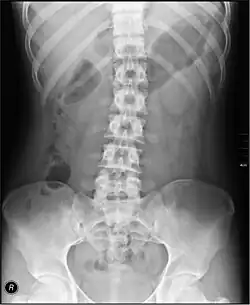

Las enfermedades que afectan al intestino grueso pueden hacer que la sangre salga con las heces, pueden causar estreñimiento o pueden provocar dolor abdominal o fiebre. Las pruebas que examinan específicamente la función del intestino grueso incluyen tragos de bario, rayos X abdominales y colonoscopia.[3]: 913–915